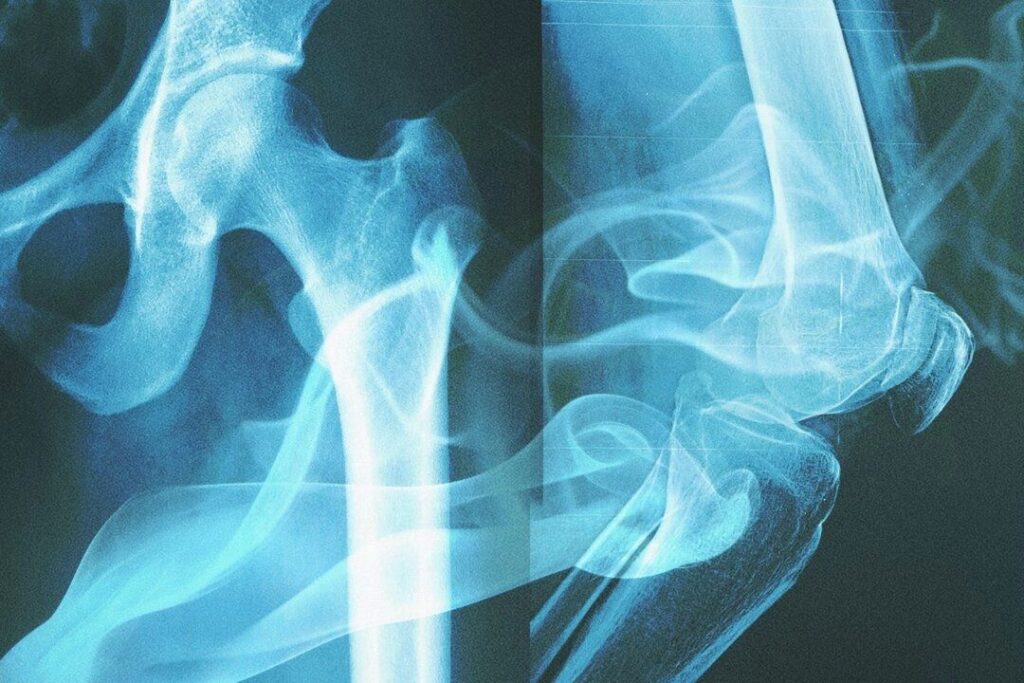

研究チームは各個体の大腿骨(太ももの骨)から、お米一粒ほどの重さである約40mgの皮質骨を抽出し、液体クロマトグラフィー高分解能質量分析法で検査しました。この技術は、サンプル内の化学物質を質量や構造で分離し、正確に特定することができます。